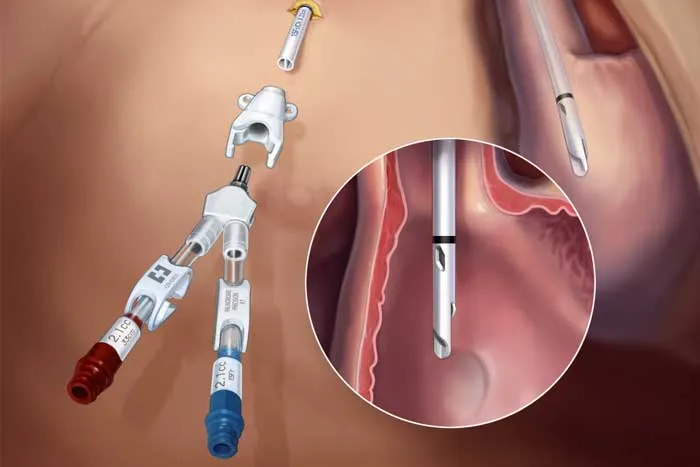

A DRPAD não é contraindicação à DP — e, na prática, muitos pacientes têm resultados comparáveis à hemodiálise. O “porém” está na mecânica: rins/hepatomegalia podem reduzir tolerância a volumes, aumentar risco de hérnias e extravasamentos, e piorar desconforto respiratório. Com técnica adequada (cateter presternal ou lateral, volumes menores, cicladora noturna e decúbito supino), a maioria das barreiras é contornável. Neste post, revisamos quando a DP é ótima, quando exigir cautela e como ajustar a prescrição para segurança e qualidade de vida.